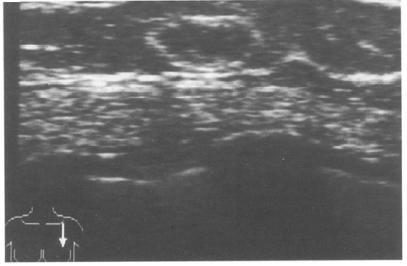

An asymptomatic 63-year-old woman attended for her first screen as part of the National Health Service Breast Screening Programme. Mammograms showed involuted breasts with a 20mm, well defined opacity in the lower inner quadrant of her left breast (Fig. 1). The opacity contained fine punctate microcalcification and localized compression views demonstrated a halo, suggesting it was benign. Although the patient was unaware of its presence the mass was palpable as a smooth, well defined lesion. Ultrasound examination showed a well defined, solid, mainly hypoechoic lesion containing small, bright echoes consistent with areas of calcification (Fig. 2).

Fig. 2 - Ultrasound image of the well defined mass